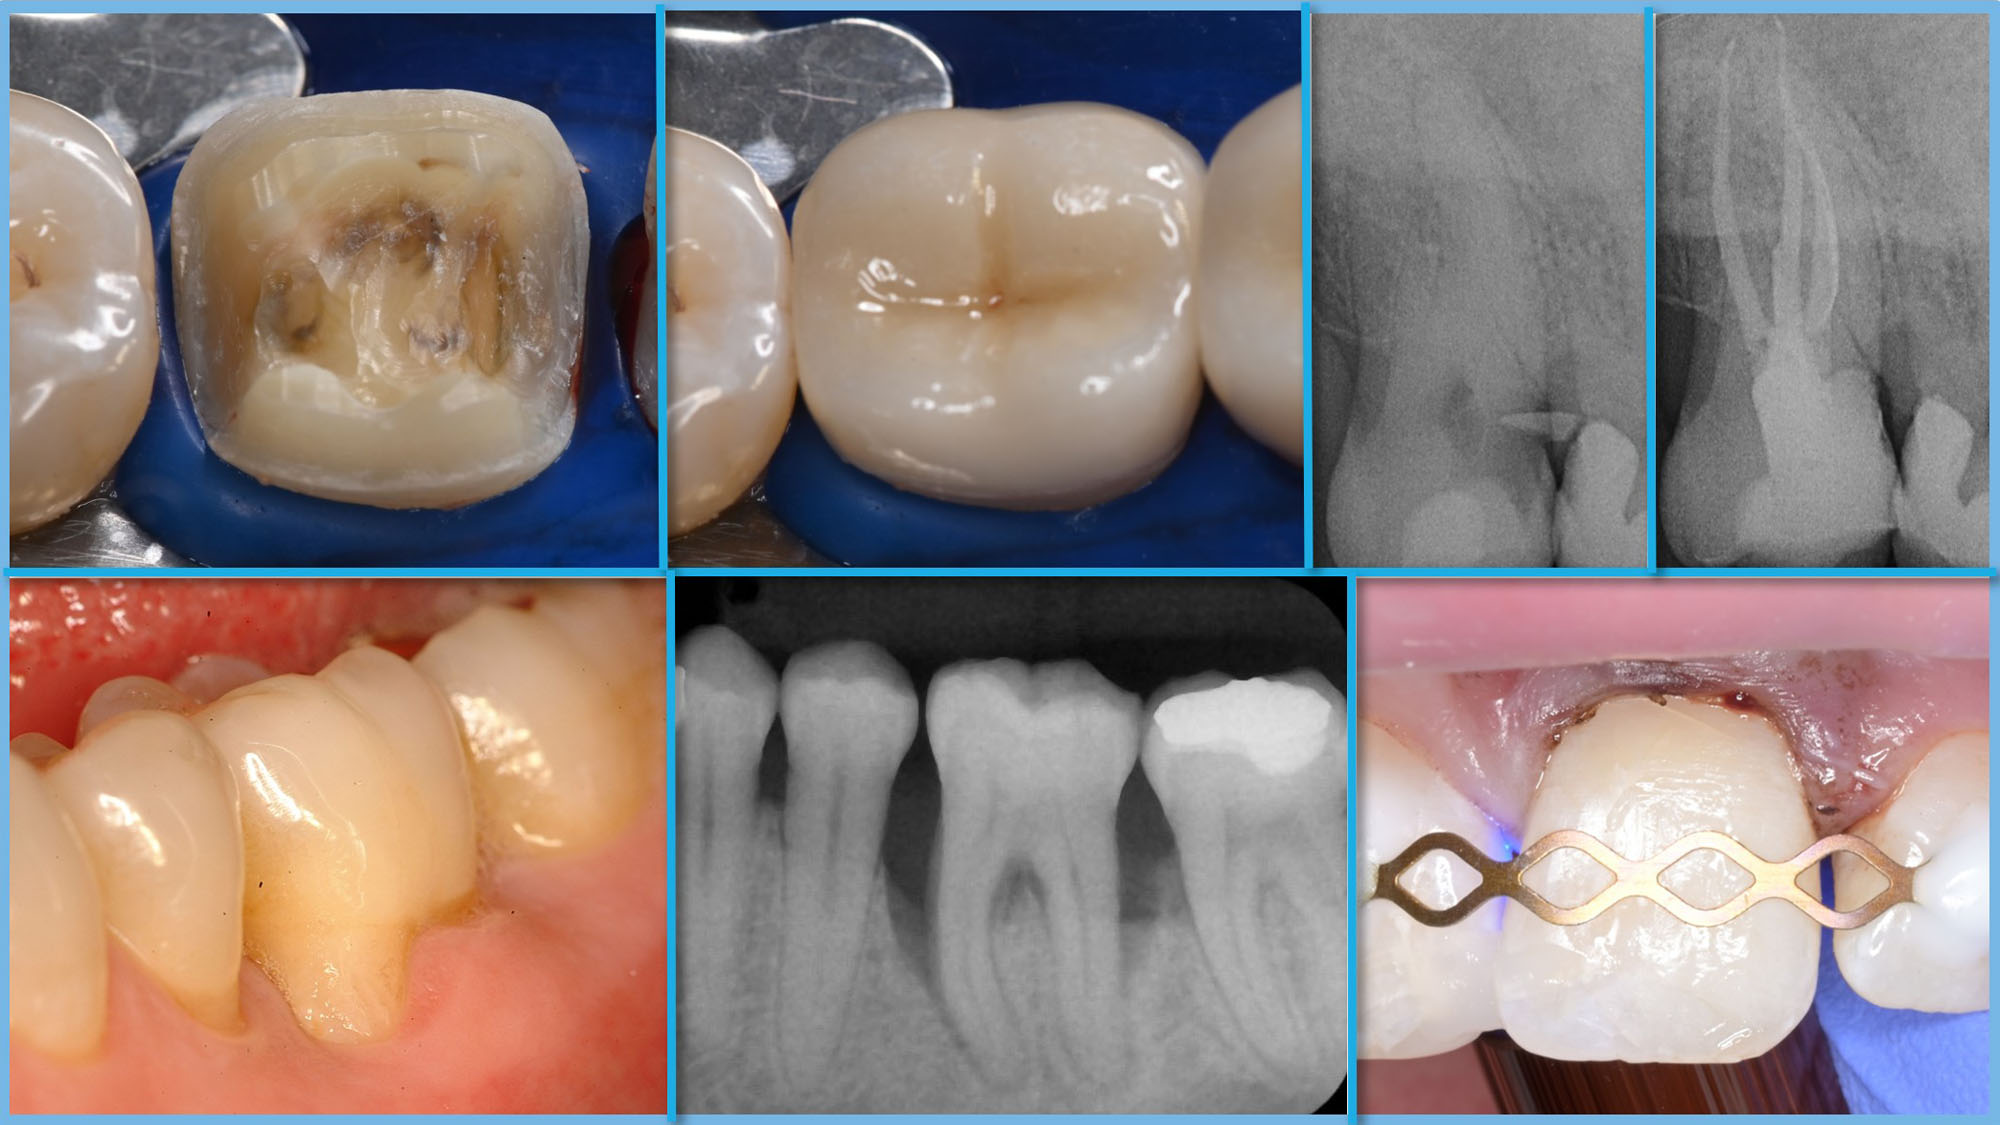

Zahnerhaltung (M.Sc.)

Restauration – Parodontologie – Endodontie – Prävention und Kinderzahnmedizin

Abschluss Master of Science

Studienbeginn Wintersemester

Zugang Qualifikationsfeststellungsverfahren

Fachbereich Zahnmedizin